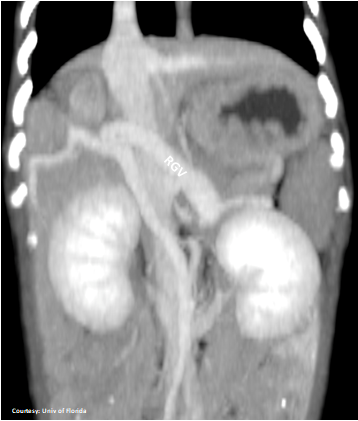

Does the RIGHT GASTRIC VEIN (RGV) contribute blood to the shunt?

“aLGC +RGV”

Aberrant Left Gastric-Caval Shunt with Right Gastric Vein contribution

Alternate (Pancreatic vein contribution as well): “aLGC +RGV +PancV”